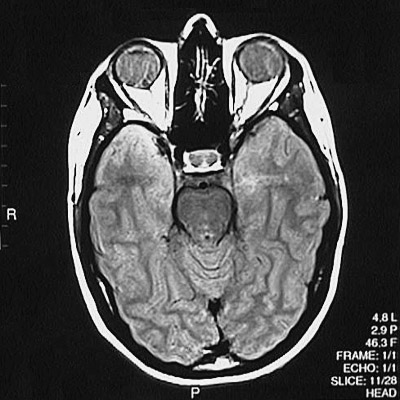

This is a normal axial proton density MRI scan demonstrating the temporal lobe and occipital lobe and basis pontis and aqueduct of Sylvius and cerebellar vermis and ethmoid sinus and pituitary and orbit.